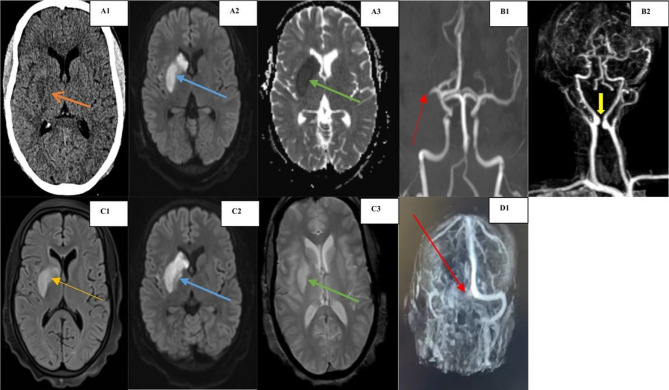

Case presentation: A 29-year-old female presented with sudden left hemiparesis and dysarthria. Index Brain MRI revealed acute non-haemorrhagic infarcts in the right middle cerebral artery (MCA) territory. Index brain MRA of cerebral vessels revealed abrupt cut off of the right MCA M1 segment following arterial thrombosis with extracranial kissing internal carotid arteries. Interval imaging of her brain and cerebral vasculature on day 4 of admission following a convulsion revealed left transverse cerebral venous sinus thrombosis. Laboratory workup confirmed low Protein S activity of only 18% (normal 55-123). She was started on rivaroxaban for lifelong secondary arterial stroke prophylaxis.